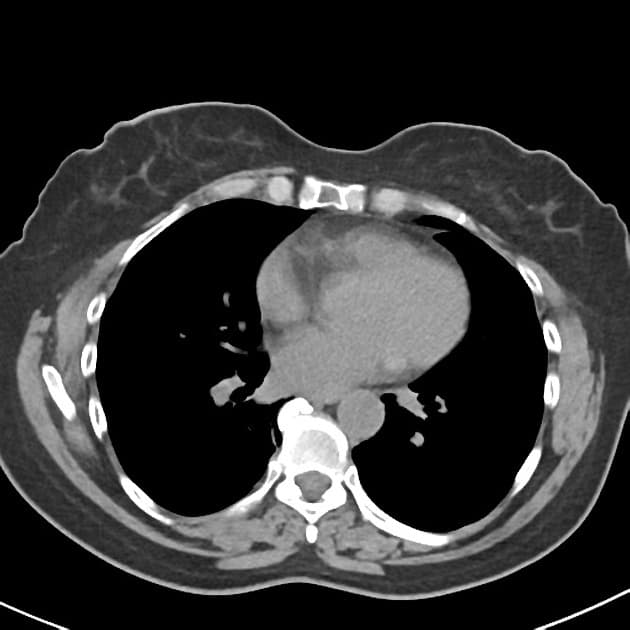

- Có giãn dạng thoi các ống mật ngoài gan (bao gồm ống mật chủ và ống gan chung) chứa nhiều ổ giảm tín hiệu trên mọi chuỗi xung, phân bố theo trọng lực, phù hợp với hình ảnh sỏi.

- Không có giãn đường mật trong gan.

- Có một tổn thương nhỏ dạng nang (tín hiệu cao trên T2, thấp trên T1 và không ngấm thuốc) ở đầu tụy, thông với một nhánh ống tụy nhỏ, phù hợp với IPMN nhánh bên (side branch IPMN).

- Không giãn ống tụy chính.

- Không thấy thành phần tăng mật độ có ngấm thuốc.

Interpretation: U nang ống mật chủ (type 1) kèm theo tổn thương IPMN nhánh bên phát hiện tình cờ (incidental side branch IPMN).

U nang ống mật chủ - type I (choledochal cyst - type I)